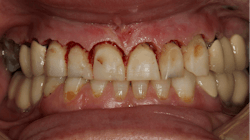

A 35-year-old female patient presented with esthetic concerns after a diagnosis of Sjögren's syndrome. Patient complaints included short appearance of teeth, stained teeth, and worn incisal edges (figures 1–2). Loss of vertical dimension of occlusion was noted as evidenced by shortened coronal structure and bilateral angular cheilitis (figure 3).

Upon clinical and radiographic examination, it was determined that the patient had a combination of caries, inflamed gingiva from desiccation, and loss of vertical dimension (figure 4). Xerostomia and insufficient home care were implicated in the patient’s elevated caries rate, as well as the presence of implants leading to implant-induced caries.